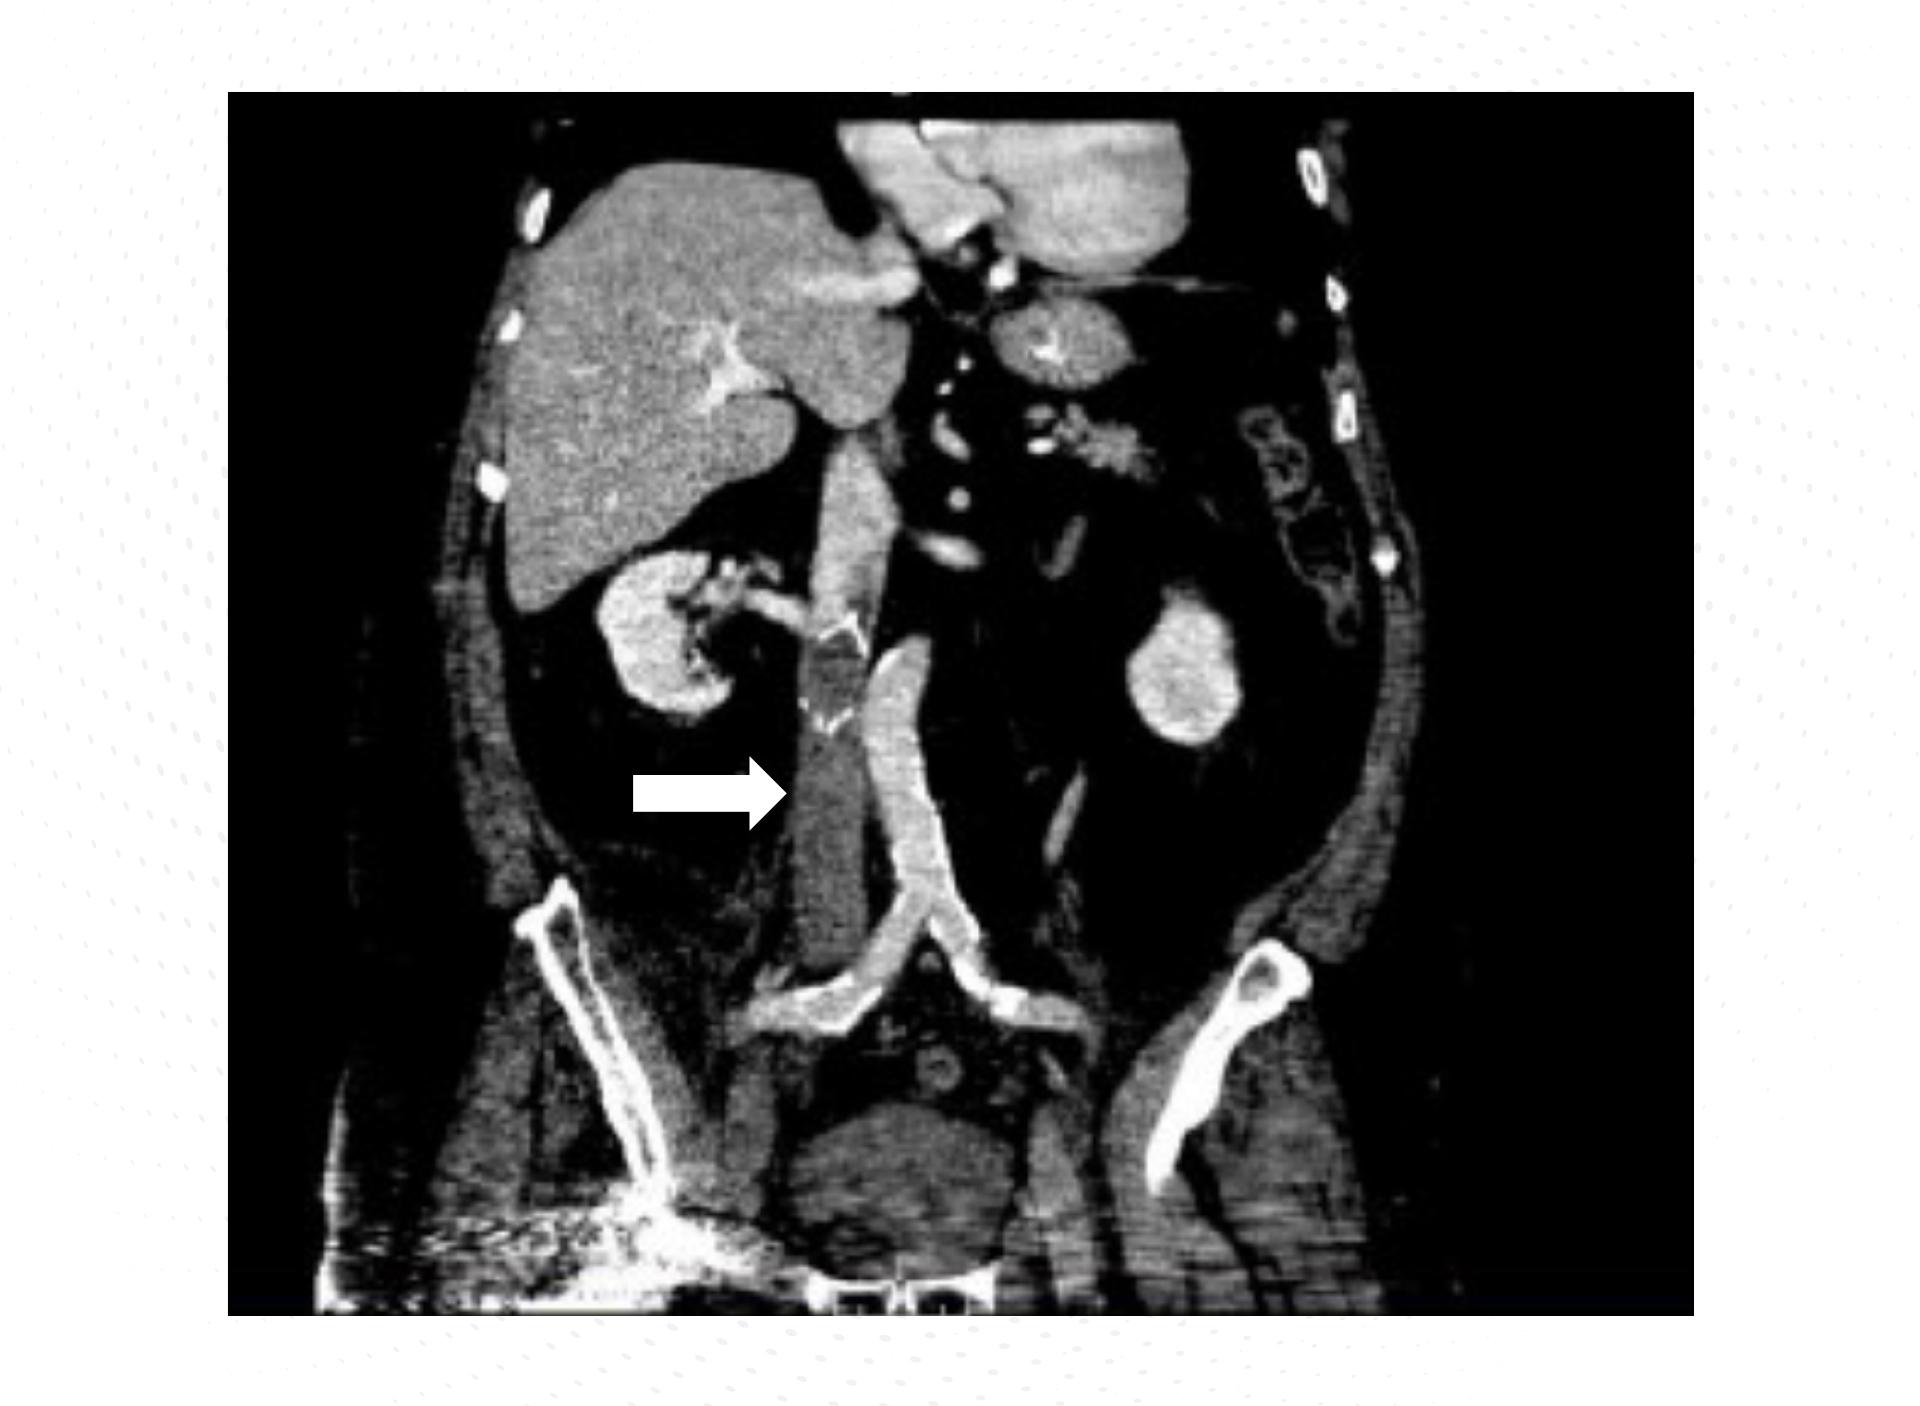

En consecuencia, no se recomienda la inserción rutinaria de un FVCI en un paciente con cáncer que sufre un TEV recurrente durante el tratamiento anticoagulante. Solo cabría planteárselo en pacientes con contraindicación para la anticoagulación a dosis plenas o en pacientes con EP recurrente y muy escasa reserva cardiopulmonar. En este último caso, siempre con anticoagulación a dosis terapéuticas o incluso supraterapéuticas de HBPM, ya que una complicación posible es la trombosis del filtro, que en el paciente con cáncer puede estar facilitada por la hipercoagulabilidad subyacente (Figura 9).